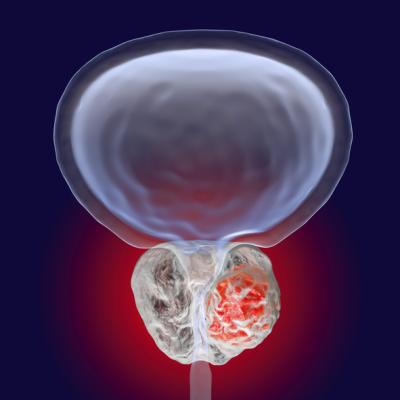

April 19, 2022 — Blue Earth Therapeutics, a Bracco company and emerging leader in the development of innovative next generation therapeutic radiopharmaceuticals, today announced that the U.S. Food and Drug Administration (FDA) has cleared the Company’s Investigational New Drug Application (IND) application for 177Lu-rhPSMA-10.1. IND authorization to proceed enables Blue Earth Therapeutics to initiate a Phase 1/2 clinical study to evaluate the safety, tolerability, dosimetry and anti-tumor activity of 177Lu-rhPSMA-10.1 in men with metastatic castrate-resistant prostate cancer (mCRPC). 177Lu-rhPSMA-10.1 is the first clinical candidate in Blue Earth Therapeutics’ oncology development program of next generation therapeutic radiopharmaceuticals. Blue Earth Therapeutics holds exclusive worldwide rights to therapeutic applications of radiohybrid Prostate-Specific Membrane Antigen (rhPSMA) radiopharmaceutical technology to help advance the treatment of patients with prostate cancer.

“Clearance to proceed with this first clinical study for 177Lu-rhPSMA-10.1 marks an exciting milestone for our new company, Blue Earth Therapeutics, and the patients with cancer that we hope to serve,” said David E. Gauden, D.Phil., Chief Executive Officer of the Company. “We consider 177Lu-rhPSMA-10.1 to be a next generation PSMA therapy with the potential to be best-in-class. 177Lu-rhPSMA-10.1 is the result of a careful optimization process which aimed to maximize therapeutic index by delivering high radiation doses to prostate cancer lesions while sparing normal tissues wherever possible. Excitingly, this optimized technology can be developed with both beta- and alpha-emitting therapeutic radioisotopes. We look forward initially to applying our proven radiopharmaceutical development expertise in advancing 177Lu-rhPSMA-10.1, and, over time, developing a pipeline of additional oncology therapeutics to help address significant unmet patient needs.”

The trial is an open-label, multi-center, integrated Phase 1 and 2 study to evaluate the safety, tolerability, radiation dosimetry and anti-tumor activity of 177Lu-rhPSMA-10.1 in men with metastatic castrate-resistant prostate cancer. Phase 1 will investigate the safety, tolerability and dosimetry of multiple cycles of 177Lu-rhPSMA-10.1 in subjects with PSMA-positive mCRPC which has progressed following prior therapy. Results from Phase 1 will be used to determine the recommended treatment regimen to be tested in Phase 2. The Phase 1 study will be conducted at clinical sites in the United States, with further sites added for the Phase 2 component of the trial, in both the United States and Europe.

rhPSMA compounds are referred to as radiohybrid (“rh”), as each molecule possesses three distinct domains. The first consists of a Prostate-Specific Membrane Antigen-targeted receptor ligand which attaches to and is internalized by prostate cancer cells. It is attached to two labelling moieties which may be radiolabeled with either 18F for PET imaging, or with isotopes such as 177Lu or 225Ac for therapeutic use – creating a true theranostic technology. They may play an important role in patient management in the future, and offer the potential for precision medicine for men with prostate cancer. Radiohybrid technology and rhPSMA originated from the Technical University of Munich, Germany. Blue Earth Diagnostics acquired exclusive, worldwide rights to rhPSMA diagnostic imaging technology from Scintomics GmbH in 2018, and therapeutic rights in 2020, and has sublicensed the therapeutic application to its sister company Blue Earth Therapeutics. Blue Earth Therapeutics and Blue Earth Diagnostics work closely on the development of 177Lu-rhPSMA-10.1. Currently, rhPSMA compounds have not received regulatory approval.